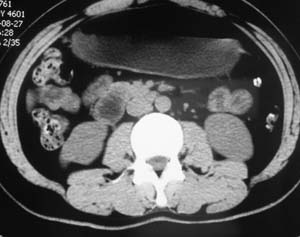

以下是引用子期在2010-3-19 20:47:00的发言:[br]血管畸形的ct增强应该有明显强化,本例并不相符合。本例双肾局部的略低密度影,累及肾盂,局部皮质明显变薄、内陷,增强扫描有轻度的强化,应考虑为炎性病变,患者为年轻男性,累及双肾的感染以结核较常见,可以没有明显的临床症状,尿中有时候也并不能查出什么;肾脓肿常有明显感染中毒症状,本例不符,另外一般的肾盂肾炎或肾小球肾炎通过小便就可确诊,其它还不能排除的是黄色肉芽肿性肾盂肾炎,然而单凭ct一般也很难鉴别。